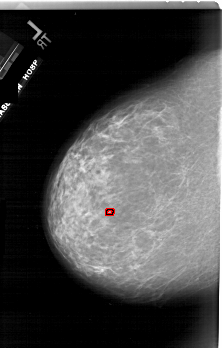

ics_version 1.0 filename A-1743-1 DATE_OF_STUDY 11 7 1996 PATIENT_AGE 69 FILM FILM_TYPE REGULAR DENSITY 3 DATE_DIGITIZED 3 3 1999 DIGITIZER HOWTEK 43.5 SEQUENCE LEFT_CC LINES 6601 PIXELS_PER_LINE 4201 BITS_PER_PIXEL 12 RESOLUTION 43.5 OVERLAY LEFT_MLO LINES 6871 PIXELS_PER_LINE 4516 BITS_PER_PIXEL 12 RESOLUTION 43.5 OVERLAY RIGHT_CC LINES 6871 PIXELS_PER_LINE 3946 BITS_PER_PIXEL 12 RESOLUTION 43.5 NON_OVERLAY RIGHT_MLO LINES 6526 PIXELS_PER_LINE 3811 BITS_PER_PIXEL 12 RESOLUTION 43.5 NON_OVERLAY |

FILE: A_1743_1.LEFT_CC.OVERLAY TOTAL_ABNORMALITIES 1 ABNORMALITY 1 LESION_TYPE CALCIFICATION TYPE PLEOMORPHIC DISTRIBUTION CLUSTERED ASSESSMENT 4 SUBTLETY 2 PATHOLOGY BENIGN TOTAL_OUTLINES 1 BOUNDARY |